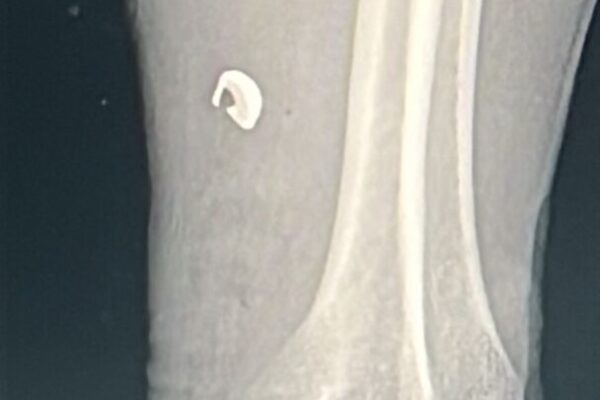

El hecho ocurrió durante la madrugada del 1 de enero; el lesionado sufrió una herida en el antebrazo izquierdo tras la detonación de un cartucho al interior de su domicilio. HISTORIASMX. Cuauhtémoc, Chihuahua.— Durante la madrugada de este 1 de enero de 2026, elementos de la Dirección de Seguridad Pública Municipal atendieron el reporte de…